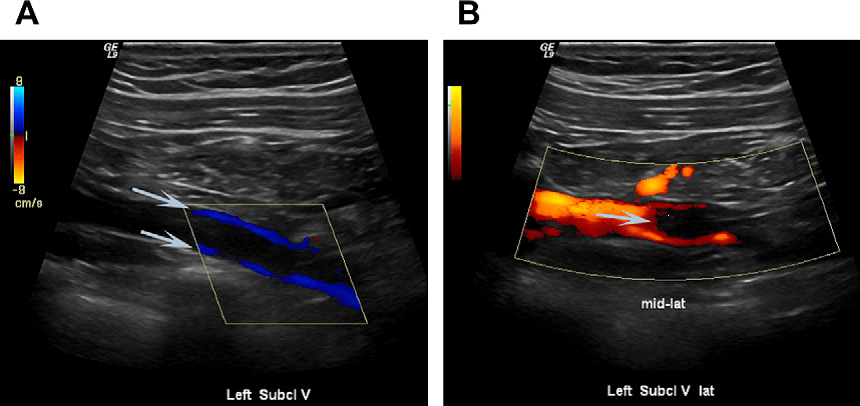

ультразвуковое дуплексное исследование вен позволяет оценить состояние венозной стенки и ее просвета, определить наличие тромботических масс, определить их локализацию, протяженность тромба, объем вовлеченных в патологический процесс тканей;

Ультразвуковое дуплексное сканирование является основным методом исследования при патологии вен, которое отличается высокой информативностью и безопасностью для пациента.

Материал и методы. В нашей клинике этот метод используется с 1998 г. С 2009 по 2013 г. было выполнено 10 509 исследований. В 2821 случае подтверждена варикозная болезнь, в 964 — посттромботическая болезнь, в 1740 — венозный тромбоз. Ультразвуковое дуплексное сканирование — это также основной метод обследования при подозрении на венозный тромбоз. Важнейшей задачей исследования в этой группе пациентов явилось выявления тромбированных вен. Тромбоз чаще был протяженным и захватывал один или несколько венозных сегментов. При исследовании в В-режиме просвет вены частично или полностью заполнялся гиперэхогенными неоднородными структурами. Окклюзия сосуда чаще сопровождалась увеличением диаметра вены, отсутствием движения ее стенок при глубоком дыхании и компрессии датчиком.

Самым важным этапом диагностики, на наш взгляд, являлась визуализация головки тромба, которую удалось оценить в 1122 случаях. У 246 (21,9%) пациентов выявлена флотация головки тромба. Достоверным признаком флотирующего тромба в В-режиме мы считаем отсутствие фиксации к стенкам вены и выявление его движений в просвете сосуда в поперечном и продольном направлениях. В ряде случаев выявлению флотации способствовало проведение исследования в вертикальном положении (если позволяло состояние больного) или осторожное проведение пробы Вальсальвы, а также компрессия проксимально расположенных мышечных массивов конечностей. В прогнозировании эмбологенности головки тромба большое значение придавали протяженности ее флотации и диаметру основания. Широкое основание и длину до 3 см мы расценивали как прогностически благоприятные признаки, позволявшие у некоторых пациентов отсрочить оперативное лечение, а в 167 (68%) случаев воздержаться от него.

Инструментальные исследования • Дуплексное ультразвуковое ангиосканирование с использованием цветного допплеровского картирования — метод выбора в диагностике тромбоза ниже уровня паховой связки. Основной признак тромбоза: обнаружение эхопозитивных тромботических масс в просвете сосуда. Эхоплотность возрастает по мере увеличения «возраста» тромба •• Перестают дифференцироваться створки клапанов •• Диаметр пораженной вены увеличивается в 2–2,5 раза по сравнению с контралатеральным сосудом, вена перестаёт реагировать на компрессию датчиком (признак, особенно важный в первые дни заболевания, когда тромб визуально не отличим от нормального просвета вены) •• Неокклюзионный пристеночный тромбоз хорошо выявляется при цветном картировании — пространство между тромбом и стенкой вены прокрашивается синим цветом •• Флотирующая проксимальная часть тромба имеет овальную форму и располагается центрально в просвете сосуда • Рентгеноконтрастная ретроградная илиокаваграфия применяется в тех случаях, когда тромбоз распространяется выше проекции паховой связки, поскольку УЗИ тазовых сосудов затрудняется из-за кишечного газа.

Цветовая дуплексная сонография и ультразвуковое допплеровское исследование — дают максимум информации о состоянии венозных путей и прилегающих тканей, места расположения тромба, объёма распространения.